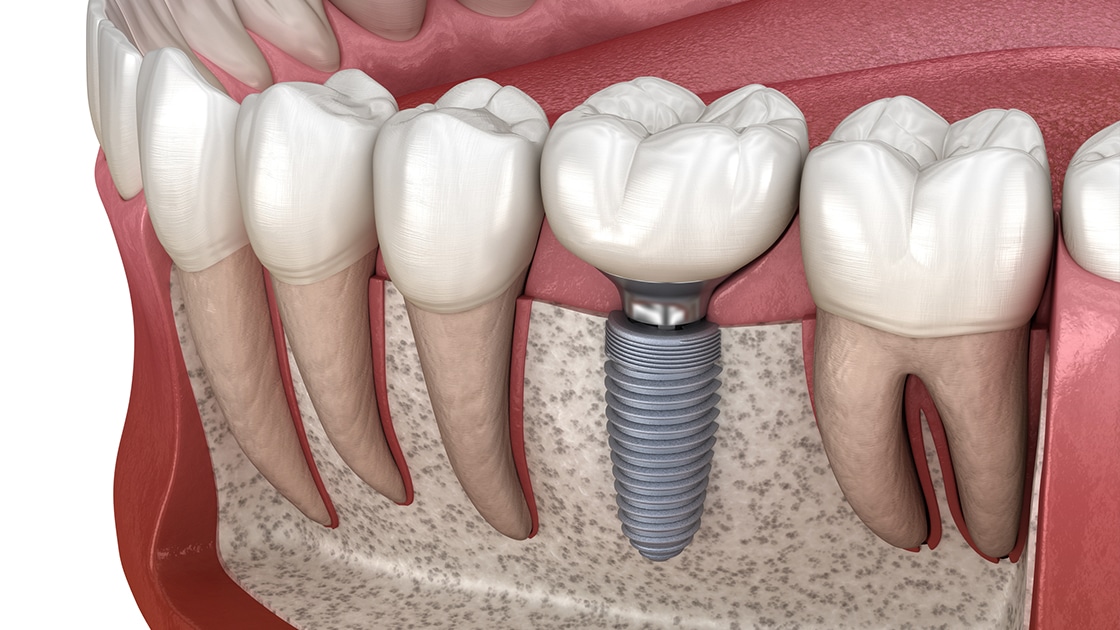

آیا به دنبال راه‌حلی دائمی برای جایگزینی دندان‌های ازدست‌رفته‌تان هستید؟ ایمپلنت دندان توسط دکتر زیبا نورعلی، با بالاترین دقت و تکنولوژی روز، بهترین گزینه برای شماست.

مهارت در ایمپلنت‌های دندانی

ایمپلنت‌های دندانی یکی از مهم‌ترین مهارت های دکتر نورعلی است. او با استفاده از مواد باکیفیت و تکنیک‌های جراحی پیشرفته، ایمپلنت‌هایی با دوام و ظاهری کاملاً طبیعی را برای بیماران خود انجام می‌دهد. درصد بالای موفقیت در کاشت ایمپلنت‌ها به دلیل مهارت و تجربه گسترده او در این زمینه است.